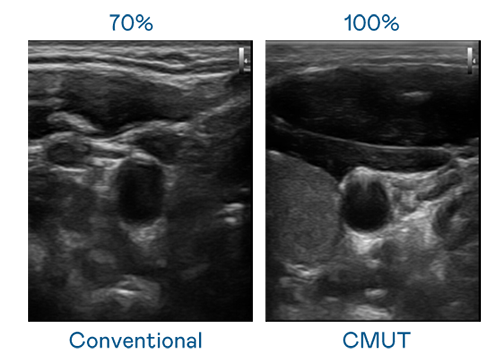

CMUT 技术是一种用电容式微机电元件来产生超音波讯号的技术。与传统 PZT 压电式技术相比,CMUT 频宽增加 30%,更宽频的超音波讯号让影像解析度大幅提升,是实现高影像品质医疗超音波扫描、促进精准医疗发展的关键技术。

超音波影像的解析度高低,首先取决于探头能发出的讯号频宽。www.乐鱼 CMUT 可提供高清晰的超音波讯号,提供高频宽、高灵敏度、影像纹理细节更高的超音波影像,协助医护人员缩短影像判读时间及利用精准的医疗影像进行诊断。